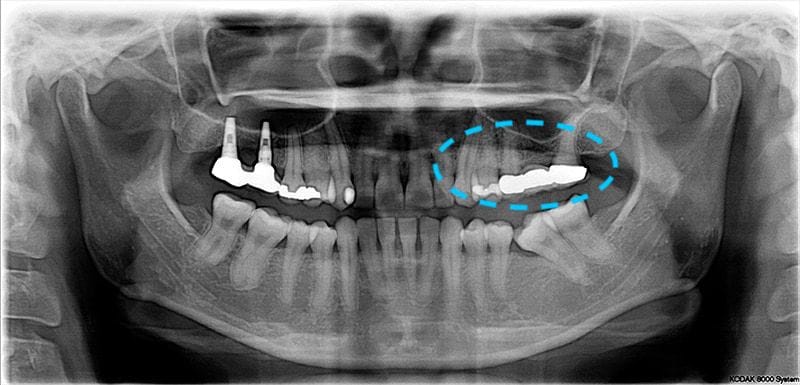

Miss Feng也是很怕看牙,因此即使自己知道牙齒有問題,也會一直拖延到沒辦法忍耐才會看醫生。2015年我幫她看診時,最主要的問題有兩個:第一個是左邊下顎後牙區,很容易塞食物,牙齦常常會不舒服。第二個則是在左邊上顎後方的假牙周圍,牙齦很容易流血。

從口內的檢查和全口的X光片檢查,我們可以發現她以前在右上後牙區有給其他醫師植牙的經驗,但可能還是因為怕看牙,左側就一直沒處理。

左下區域很早第一大臼齒就缺牙。因為缺牙不補,久了以後齒列空間改變,後面兩顆臼齒往前傾倒,造成吃東西時食物堆積難以清潔的問題。左邊上面後方假牙,時間久遠,密合度已經不佳,這會是清潔的死角,因而造成牙菌斑堆積導致牙齦發炎流血。

全口牙周檢查方面,齒槽骨是有初期流失,只有在主訴區域有比較深的牙周囊袋,屬於全口輕微、局部中度牙周炎。